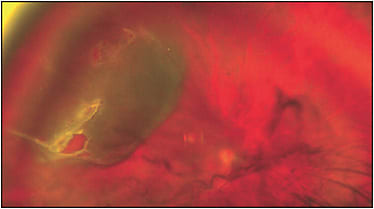

Pars plana vitrectomy (PPV) without scleral buckle surgery (SB) is the most popular treatment of uncomplicated primary rhegmatogenous retinal detachment (RRD; Figure), and its use is increasing.1 Likely contributing factors favoring PPV as the preferred surgical treatment over SB or a combined PPV/SB surgical approach include advances in small-gauge vitrectomy surgery; improved wide-angle viewing systems; avoidance of complications typically associated with scleral buckles, such as postoperative strabismus, anterior-segment ischemia, and increased myopic refraction; and reduced experience with SB during fellowship training. Single operation success rates with PPV for RRD are very high and were recently noted to range from 91% to 96%.2